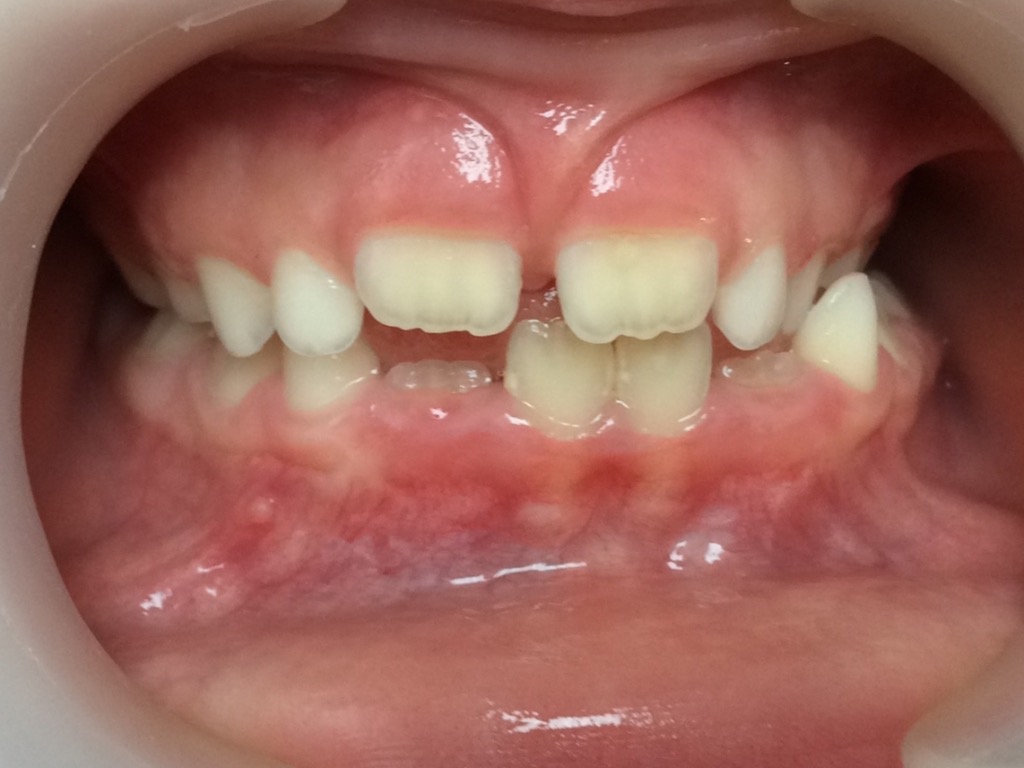

Un cas d’inversion d’articulé latéral:

Un traitement démarré à 6 ans, a permis à cette petite fille de ne pas grandir avec un menton de travers.

Photos à 6, 7 et 10 ans

Un alignement et un ajustage occlusal seront nécessaires lorsque toutes les dents définitives seront présentes.